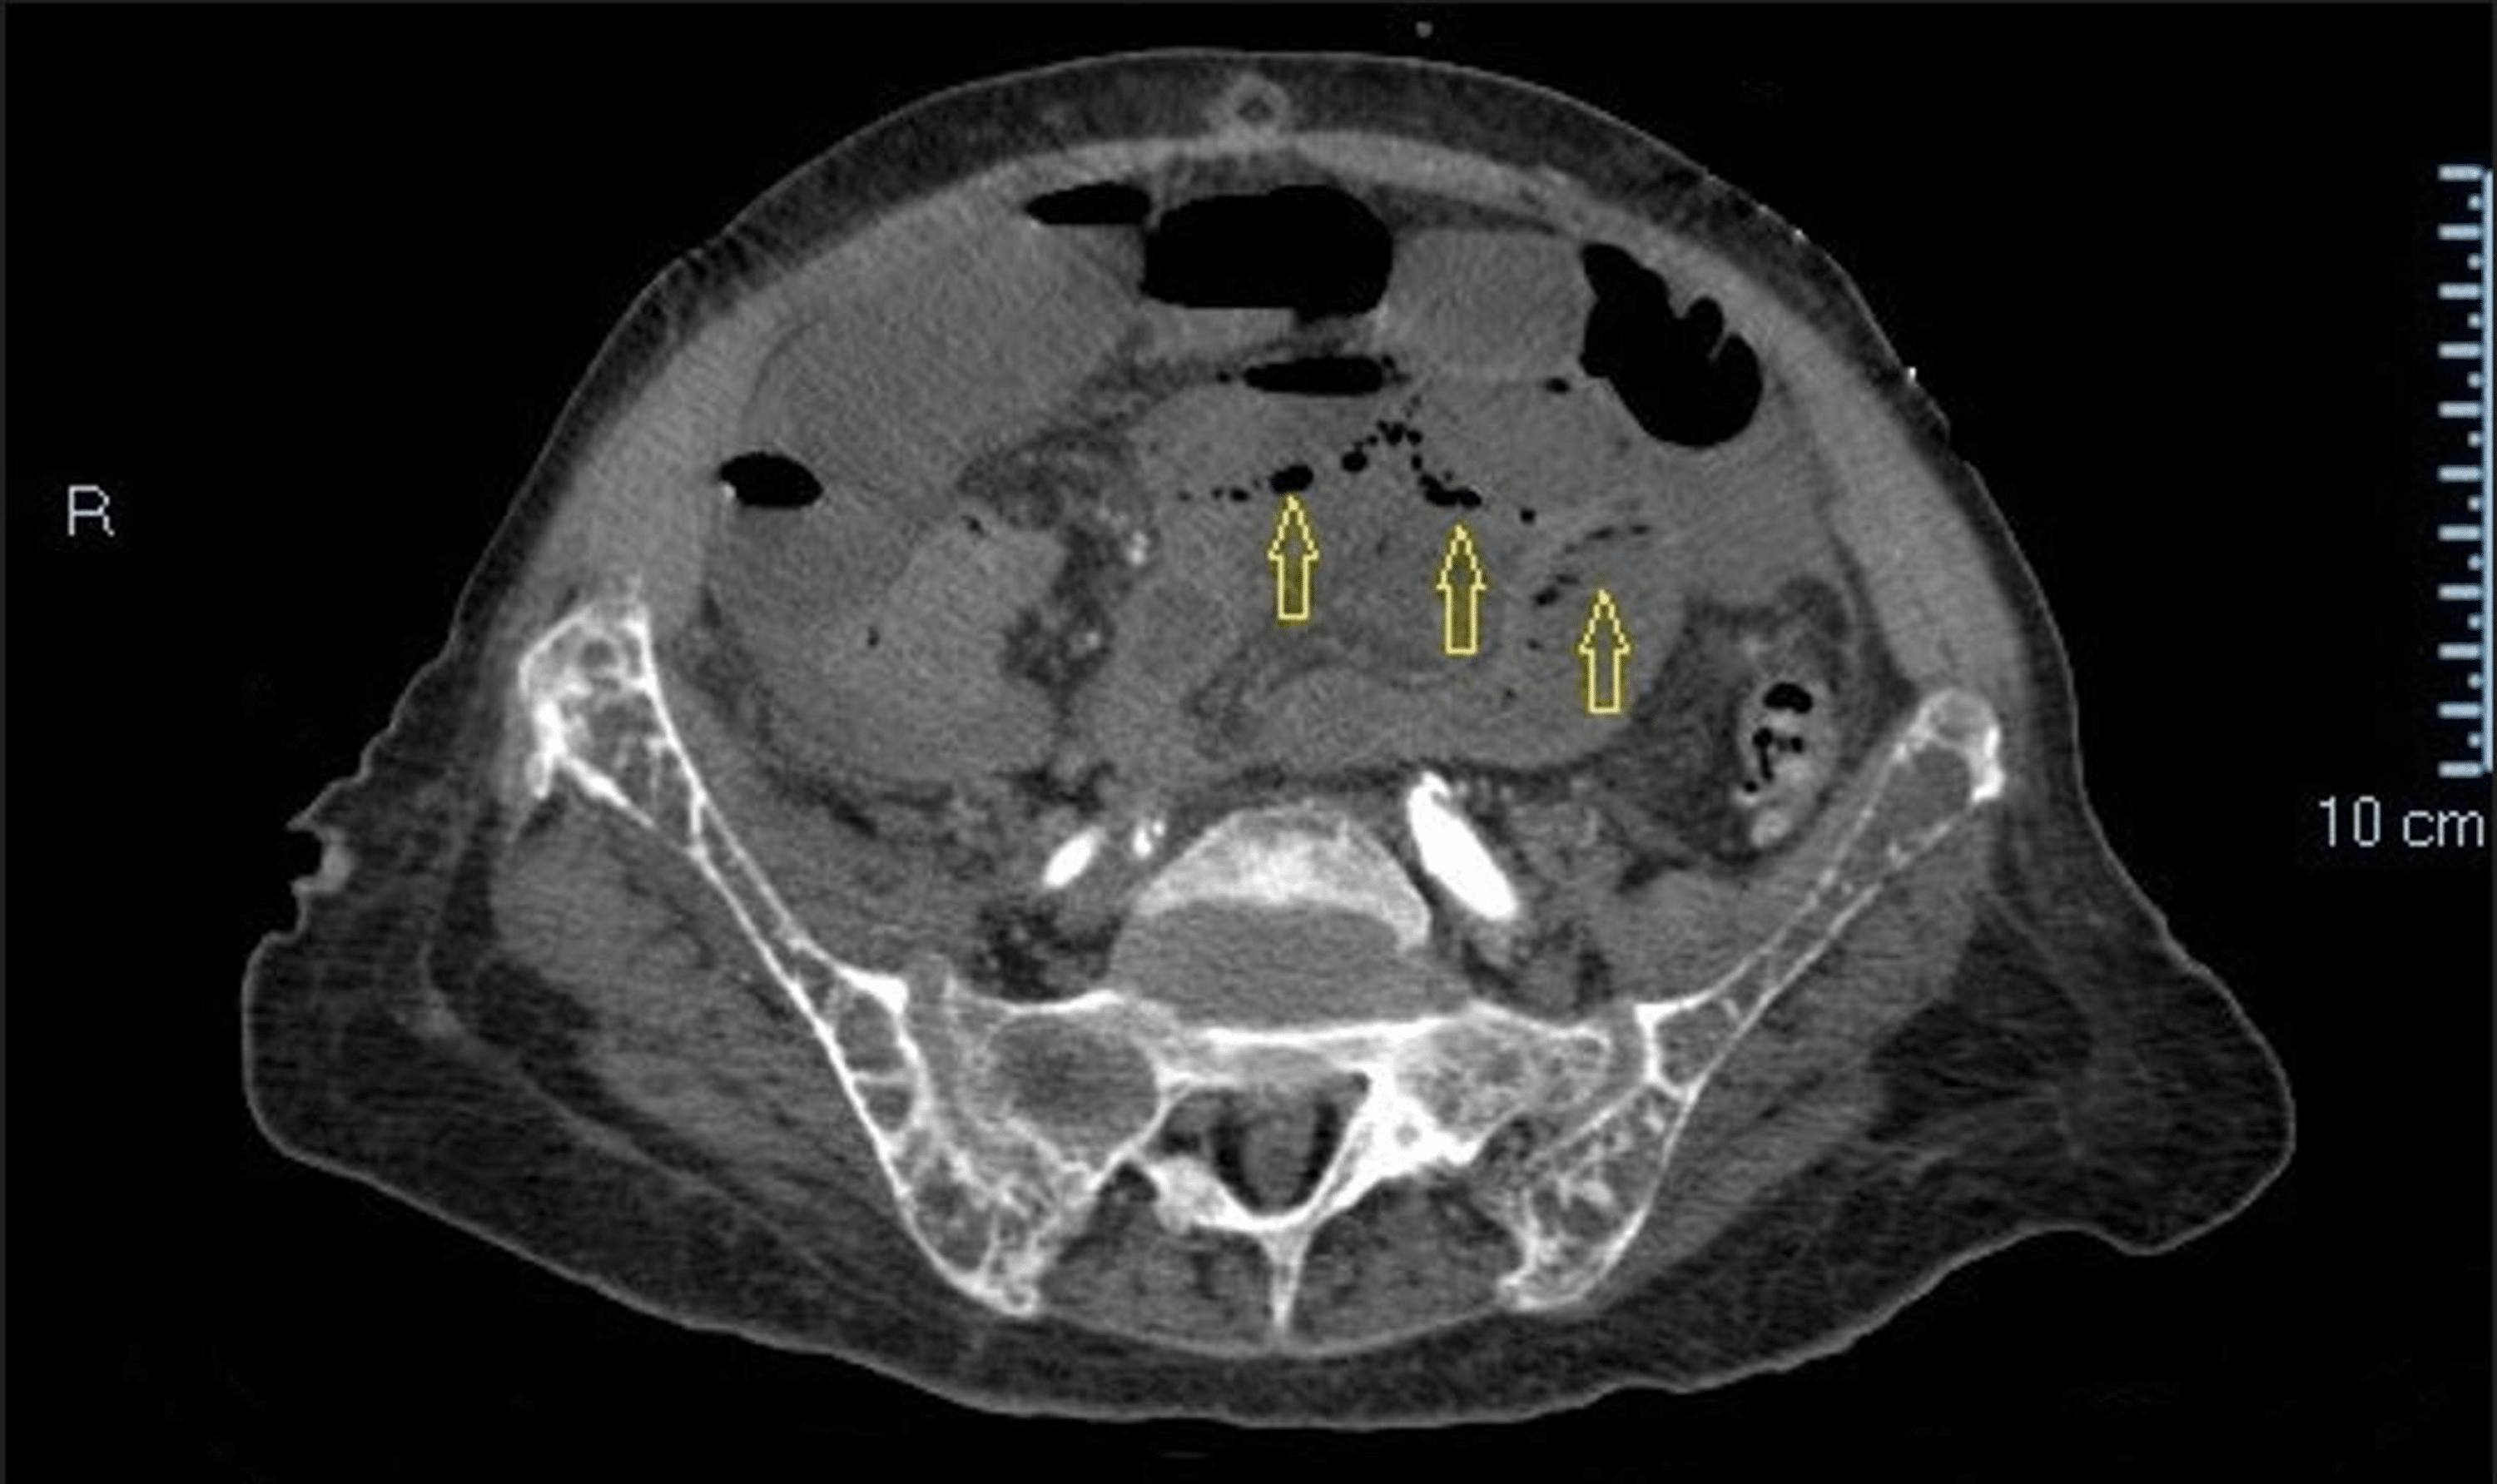

n this dialysis patient with low back pain, axial CT scan through the Severe Back Pain Dialysis Patient a detailed and comprehensive understanding of pain experiences in patients undergoing hd can inform nurses, nephrologists, and. the spectrum of pain experienced by dialysis patients is varied and may be atypical and severe, 9. Advanced age, increased body mass index, and. brkovic et al.6 examined prevalence and severity of pain in a systematic review of patients undergoing. Severe Back Pain Dialysis Patient.

n this dialysis patient with low back pain, axial CT scan through the Severe Back Pain Dialysis Patient the spectrum of pain experienced by dialysis patients is varied and may be atypical and severe, 9. in a series of four haemodialysis patients presenting with chronic backache and episodes of fever. brkovic et al.6 examined prevalence and severity of pain in a systematic review of patients undergoing hemodialysis, with. in fact, 60% to 90% of. Severe Back Pain Dialysis Patient.